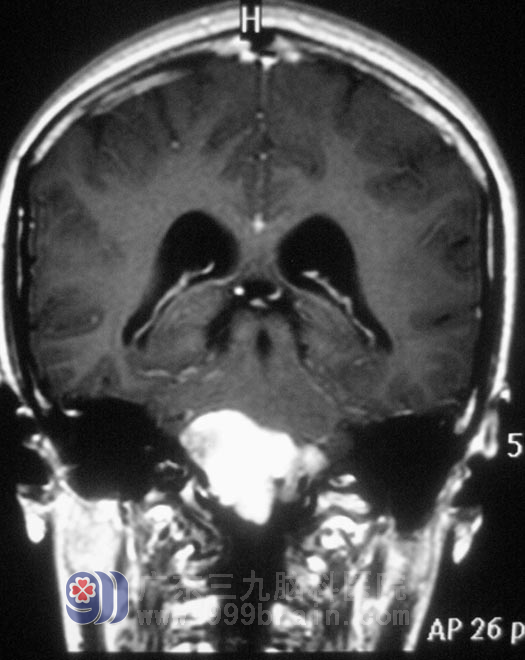

两周前,小凤出现了头痛、头晕,呈阵发性爆炸样疼痛及眩晕,一周前症状明显加重,伴恶心、间断呕吐,右下肢麻木加重。当地医院建议行颈椎MR检查,检查结果把医生都吓了一跳:小凤右侧延髓腹外侧有一占位,直径约2.7cm。在广东三九脑科医院复查MR,小凤延髓处肿瘤大小为4.19cm×2.63cm×3.74cm,伴有梗阻性脑积水,综合神经外科 鲁明主任初步考虑为胆脂瘤。